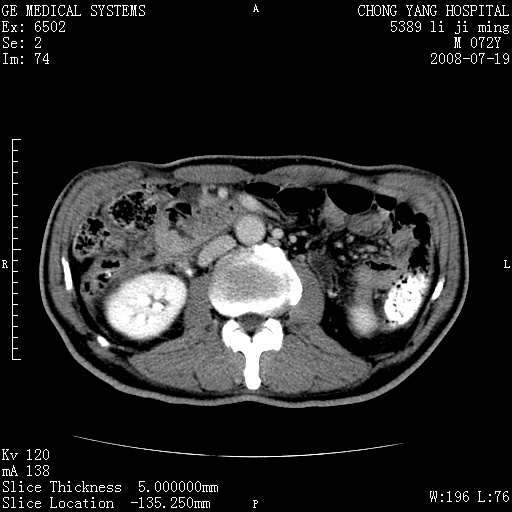

以下是引用yangyudong333在2008-7-20 6:56:00的发言:[br]胰腺增大尤以胰头明显,边缘模糊,周围可见渗出影,右侧肾前筋膜增厚,肠管於涨.支持胰腺炎

以下是引用不学无术在2008-7-19 23:15:00的发言:[br]胰腺增大尤以胰头明显,边缘模糊,周围可见渗出影,右侧肾前筋膜增厚,肠管於涨.支持胰腺炎